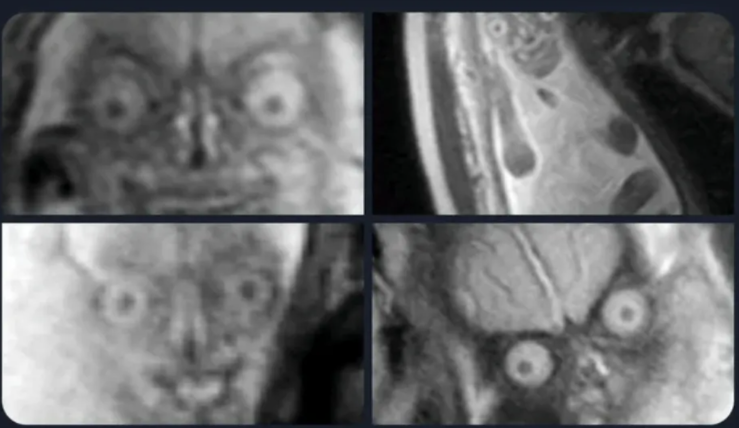

최근 온라인 커뮤니티에 올라온 “임신 중에 MRI를 찍으면 안 되는 이유”라는 제목의 게시글이 화제다.

어떤 네티즌은 자신의 SNS에 “의사가 임신 중의 MRI 촬영을 반대하는 진짜 이유는”라며 이야기를 시작했다.

이어서 “임산부가 아기가 아니라 악몽을 잉태하고 있다는 합리적 의심을 가지게 되어 두려워하는걸 방지하기 위해서가 아닐까?”라며 MRI 사진과 함께 게시글을 게시했다.

MRI 사진에는 뱃속에 있는 아이의 사진이 찍혀있었는데, 그 모습이 충격적이어서 커뮤니티 네티즌들 반응이 뜨겁다.

이를 본 온라인 커뮤니티 네티즌들은 “성인도 MRI 찍히면 저렇게 나옵니다. 좀 무섭게 보이긴 하죠.”, “관상 면으로 사람의 인체를 반으로 가른 것처럼 사진을 찍으면 당연히 호러하게 생길 수밖에 없습니다.”라는 반응을 보였다.